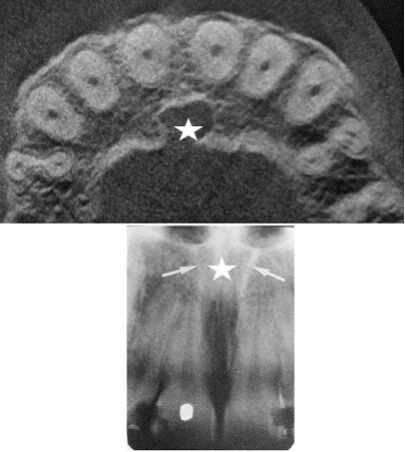

65.附圖X光影像中,星號所標示的解剖構造為何? (A)鼻腭管(nasopalatine canal)(B)鼻淚管(nasolacrimal canal)(C)鼻腭囊腫(nasopalatine cyst)(D)根尖囊腫(radicular cyst)